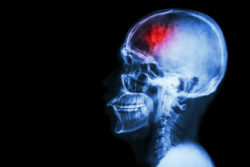

A Xarelto stroke lawsuit claims the blood thinner caused a patient injury.

The Xarelto stroke lawsuit claims that Xarelto was not safe or fit for human use as was advertised by the drug’s makers. Allegedly, Bayer and Johnson & Johnson (as well as their affiliate companies) knew or should have known that the drug was dangerous, but marketed it to patients and medical professionals nonetheless.